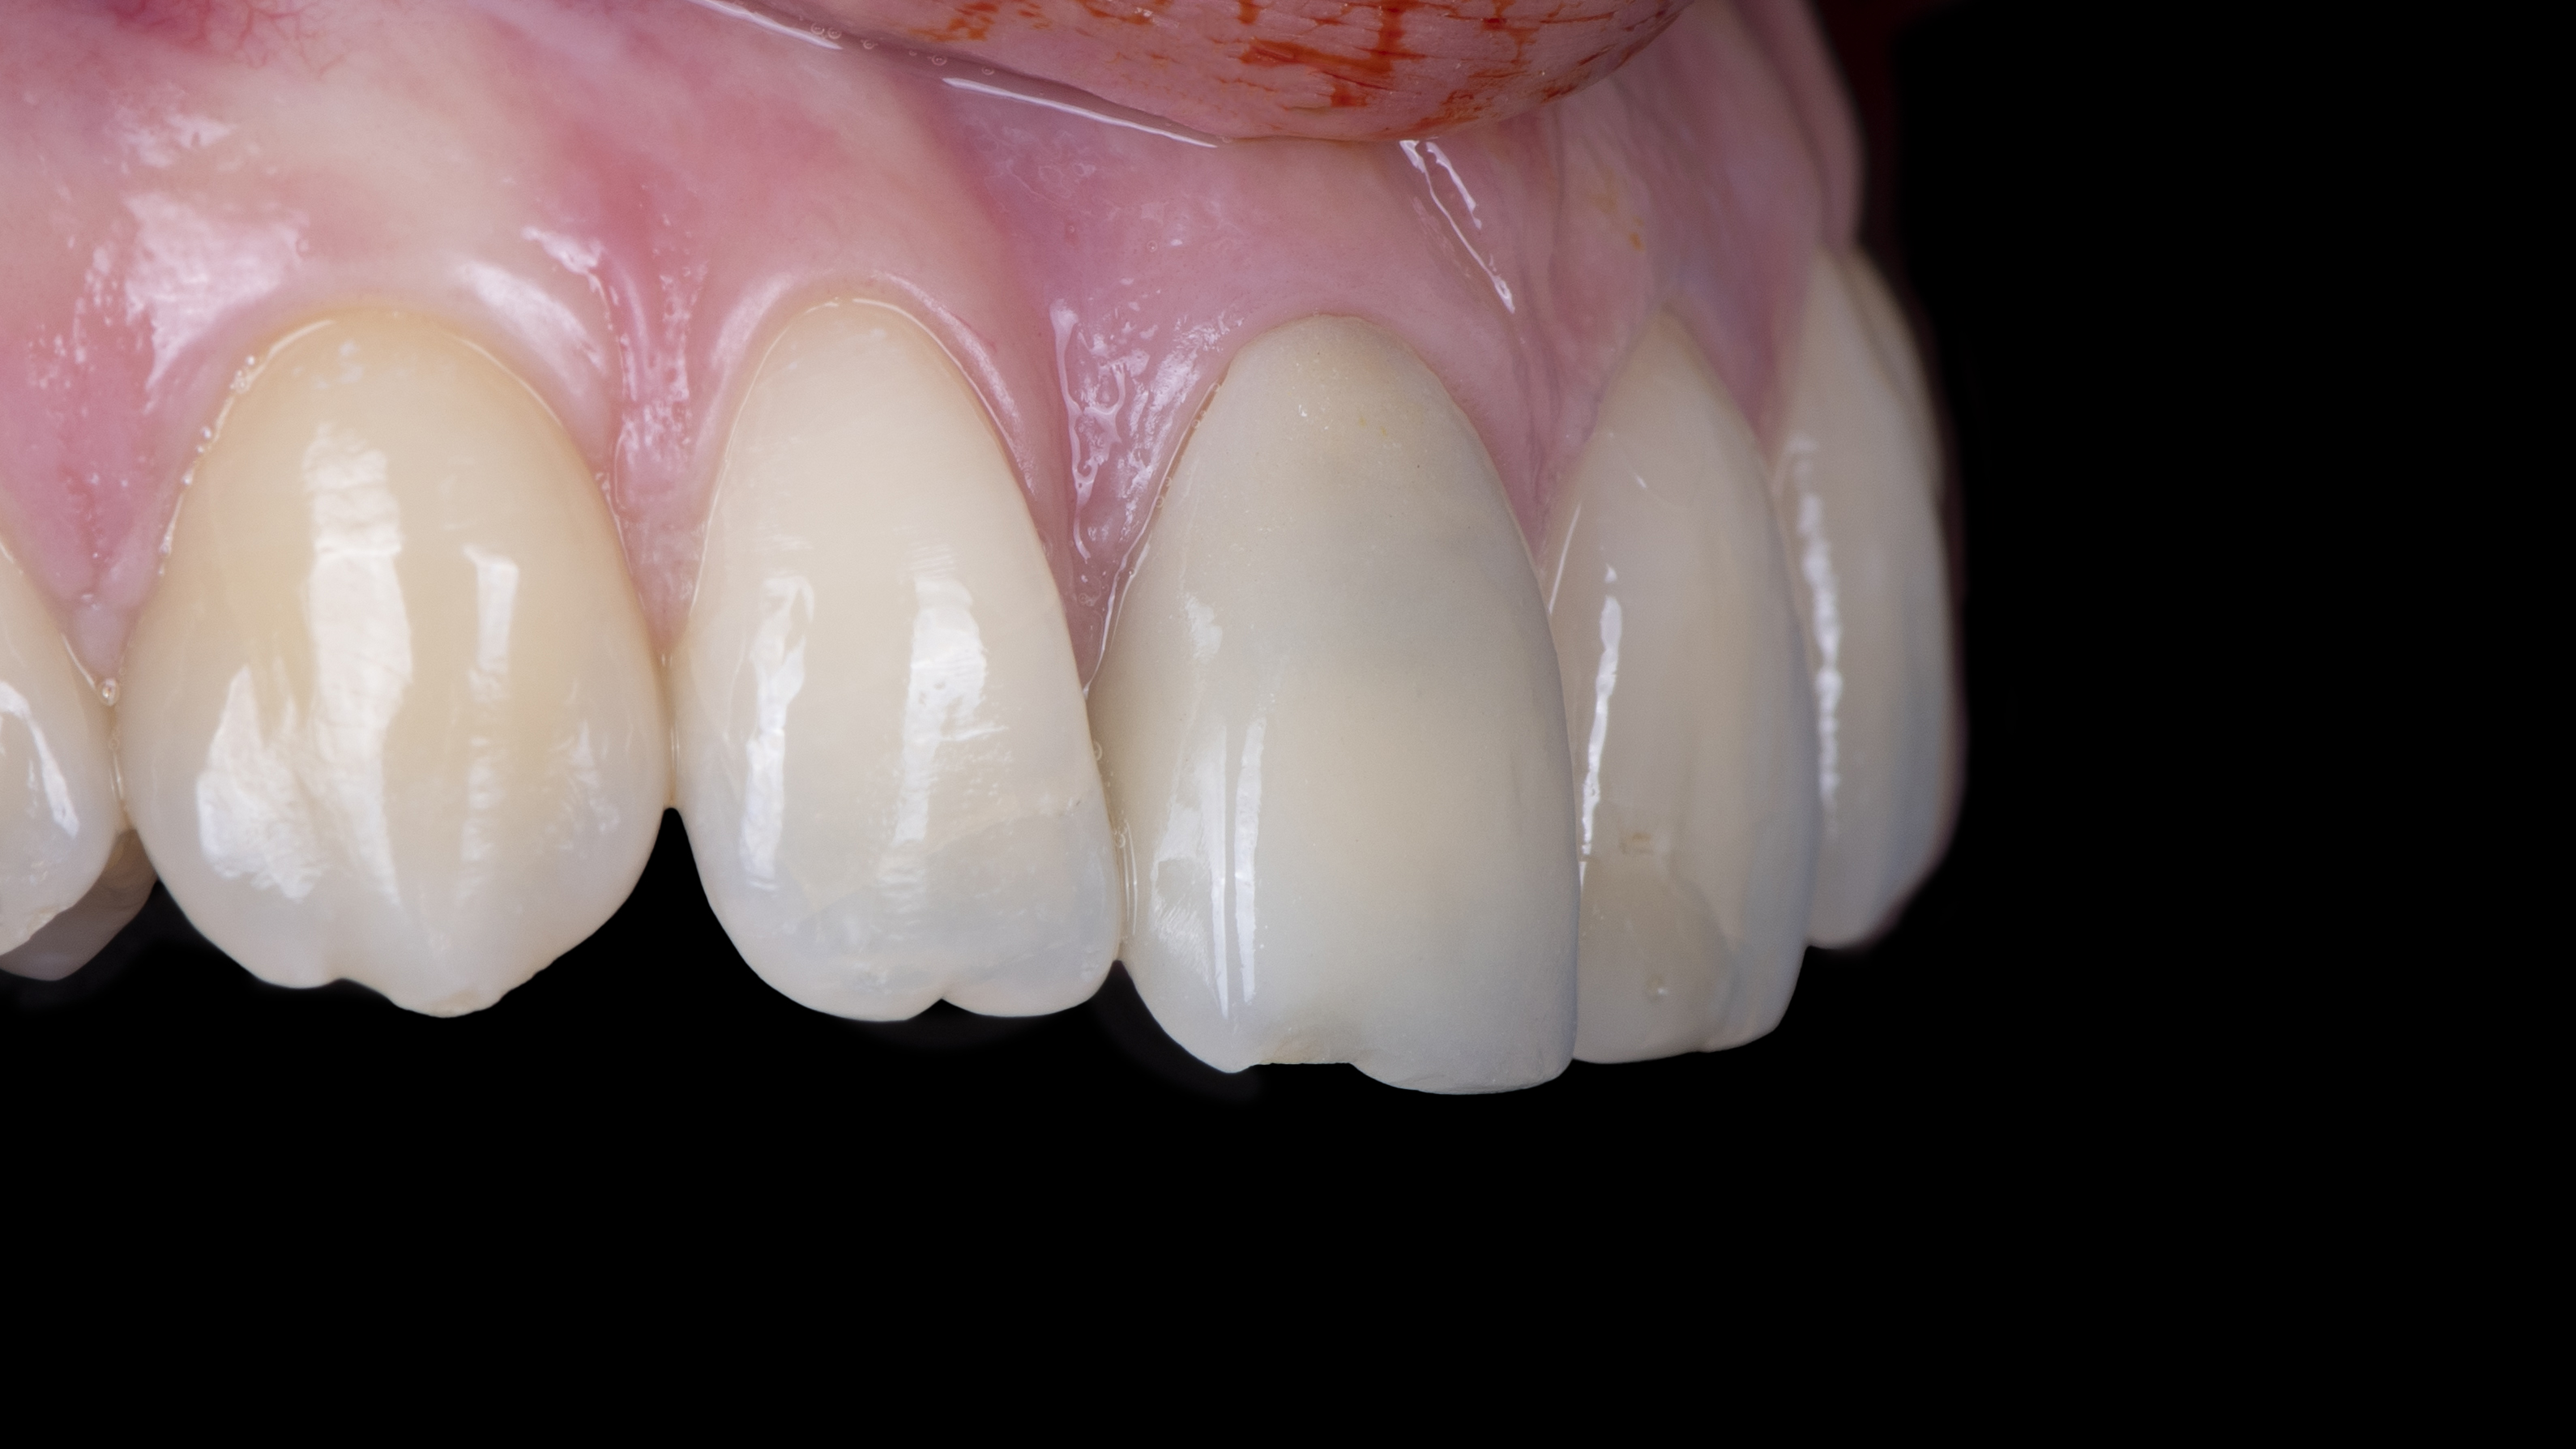

Nous constatons que la cicatrisation est alors optimale et que la prothèse d’usage s’intègre parfaitement à son environnement (Photo 20).

Intégration des réhabilitations au niveau du sourire de la patiente (Photo 26).